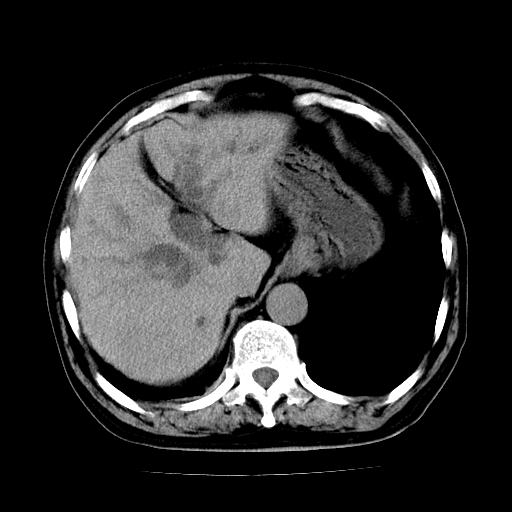

标题: CT25226:男,71岁,皮肤黄染四天。 [打印本页]

男,71岁,皮肤黄染四天。

肝内外胆管及胆总管上段扩张,考虑为梗阻所致,建议mrcp检查。

考虑胆总管癌并肝内外胆管扩张。

胰腺上端胆总管内见软组织影,强化不明显,结合临床,还是考虑低位梗阻性黄疸,胆总管癌可能性大